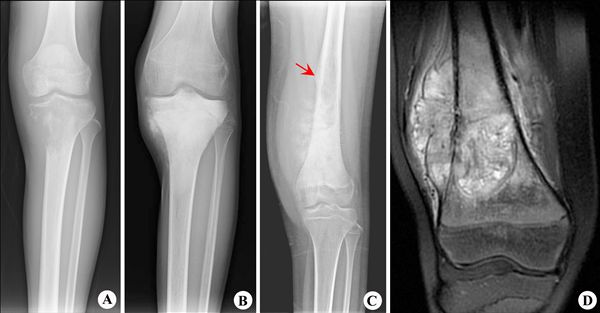

1.X线摄片

典型的骨肉瘤的X线表现为骨组织同时具有新骨生成和骨破坏的特点。肿瘤多位于长管状骨的干骺端,边缘不清,骨小梁破坏,肿瘤组织密度增高,穿破骨皮质后,肿瘤将骨膜顶起,产生该病具有特征性的X线征象--考德曼套袖状三角(Codman-三角)。这种现象在部分骨髓炎和尤文肉瘤病人中可见到,在骨肉瘤中则是非常典型的。晚期可看到肿瘤浸润软组织的阴影,可在部分病例中见到病理性骨折。

2.CT扫描和MRI检查

是判断骨肿瘤性质、范围和有无周围软组织浸润的有效手段,可早期发现肺部和其他脏器的转移病灶,是骨肉瘤临床检查的常规项目。